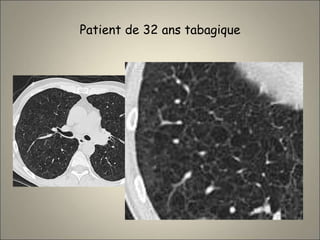

Patient de 32 ans tabagique

6 ans avant

Nodules d’histiocytose